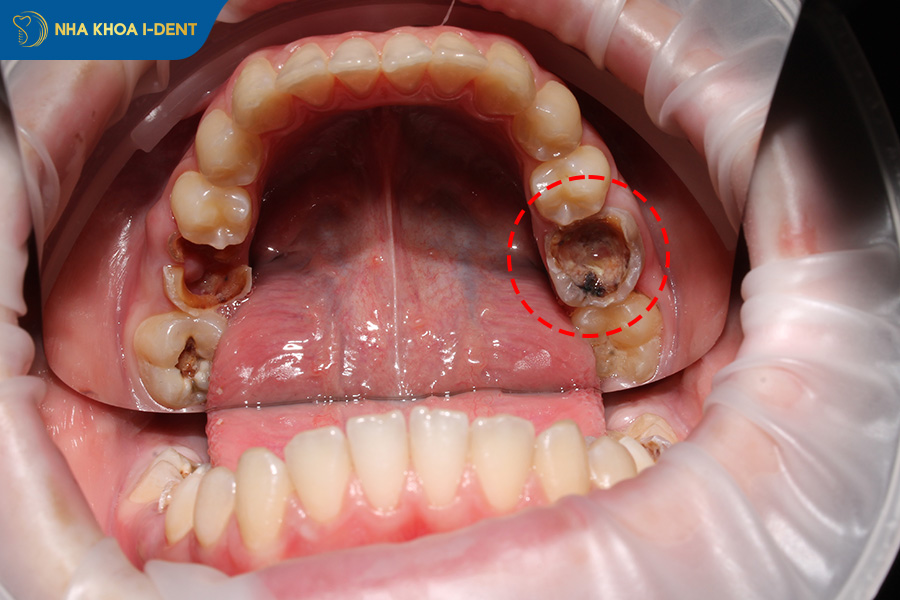

Răng hàm bị gãy khiến cấu trúc bảo vệ răng bị phá vỡ tạo điều kiện cho vi khuẩn xâm nhập vào bên trong phá hủy cấu trúc bên trong gây viêm nhiễm.

Trường hợp răng hàm bị gãy lớn và lộ cà tủy răng nhưng không điều trị phục hình kịp thời sẽ bị vi khuẩn tấn công tủy gây viêm tủy, hoại tử tủy,.. dẫn đến mất răng hàm này. Thậm chí, nhiễm trùng có thể lan rộng sang các mô xung quanh và xương hàm hình thành áp xe chân răng, viêm xương ổ răng,..

Răng hàm bị bể lớn tạo điều kiện cho vi khuẩn xâm nhập.